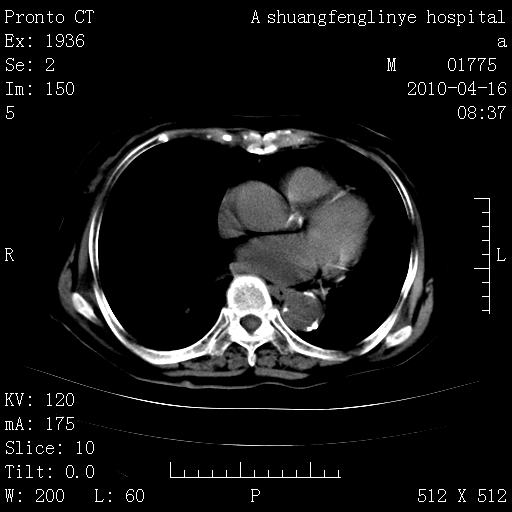

老年肺间质纤维化,肺动脉高压-----肺心病。

典型 夹层动脉瘤。 内膜瓣钙化移位

1)左肺上叶结核(纤维、增殖病灶)。2)冠状动脉及主动脉钙化。

1)左肺上叶结核(纤维、增殖病灶)。2)冠状动脉及主动脉钙化。肺动脉高压